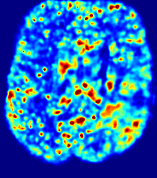

4.3.2 Diffusion Imaging via Advection-Diffusion

Slice #1Slice #2Slice #3Slice #4Slice #5Slice #6Dgtsuperscript𝐷gtD^{\text{gt}}Refer to captionRefer to captionRefer to captionRefer to captionRefer to captionRefer to captionDestsuperscript𝐷estD^{\text{est}}Refer to captionRefer to captionRefer to captionRefer to captionRefer to captionRefer to captionRefer to caption0.300.300.300.240.240.240.180.180.180.120.120.120.060.060.060.000.000.00(mm2/s)𝑚superscript𝑚2𝑠(mm^{2}/s)𝐕est𝟐subscriptnormsuperscript𝐕est2\|\bf{V}^{\text{est}}\|_{2}Refer to captionRefer to captionRefer to captionRefer to captionRefer to captionRefer to captionRefer to caption0.00300.00300.00300.00240.00240.00240.00180.00180.00180.00120.00120.00120.00060.00060.00060.00000.00000.0000(mm/s)𝑚𝑚𝑠(mm/s)

Figure 15: PIANO identifiability testing: diffusion imaging via advection-diffusion. Top row shows Dgtsuperscript𝐷gtD^{\text{gt}} used for simulating ground truth pure diffusion. Rows below show the estimated Destsuperscript𝐷estD^{\text{est}} and 𝐕est2subscriptnormsuperscript𝐕est2\|{\bf{V}}^{\text{est}}\|_{2} on corresponding slices. Note that the plotted value scale for 𝐕est2subscriptnormsuperscript𝐕est2\|{\bf{V}}^{\text{est}}\|_{2} is 0.01 of that for Dgtsuperscript𝐷gtD^{\text{gt}} and Destsuperscript𝐷estD^{\text{est}}.

Similarly, we test the behavior of PIANO when estimating both advection and diffusion from a pure diffusion-driven process. The goal is to determine if PIANO is able to recognize that there is only diffusion governing the given concentration time-series. We use the same ‘Diffusion Imaging’ data simulation of Sec. 4.2.1 as the concentration dataset, PIANO estimates both velocity 𝐕estsuperscript𝐕est{\bf{V}}^{\text{est}} and diffusivity Destsuperscript𝐷estD^{\text{est}}. Estimation results in Fig. 15 confirm PIANO’s identifiability again: the estimated 𝐕est2subscriptnormsuperscript𝐕est2\|{\bf{V}}^{\text{est}}\|_{2} is almost invisible compared to Destsuperscript𝐷estD^{\text{est}}, even plotted with a 1%percent11\% value range compared to that for Destsuperscript𝐷estD^{\text{est}}. On the other hand, Destsuperscript𝐷estD^{\text{est}} achieves comparable estimation performance as ‘Diffusion Imaging via Diffusion’ in which PIANO predicts Destsuperscript𝐷estD^{\text{est}} alone (shown in Fig. 13).